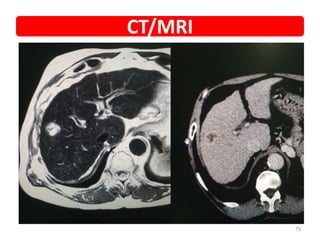

• Diagnosis • Hepatocellular carcinoma

• Presented with • Diagnosed during screening

• PET • Small lesion in segment 7

• Planned SBRT • 45Gy/3#

• PET POST SBRT 3M • Complete resolution

CT/MRI

• NAME • UMR •Diagnosis • Hepatocellular carcinoma • Presented with • Diagnosed during screening • PET • Small lesion in segment 7 • Planned SBRT • 45Gy/3# • PET POST SBRT 3M • Complete resolution • Now • f/up • COURTESY • DR VKR Case details 72